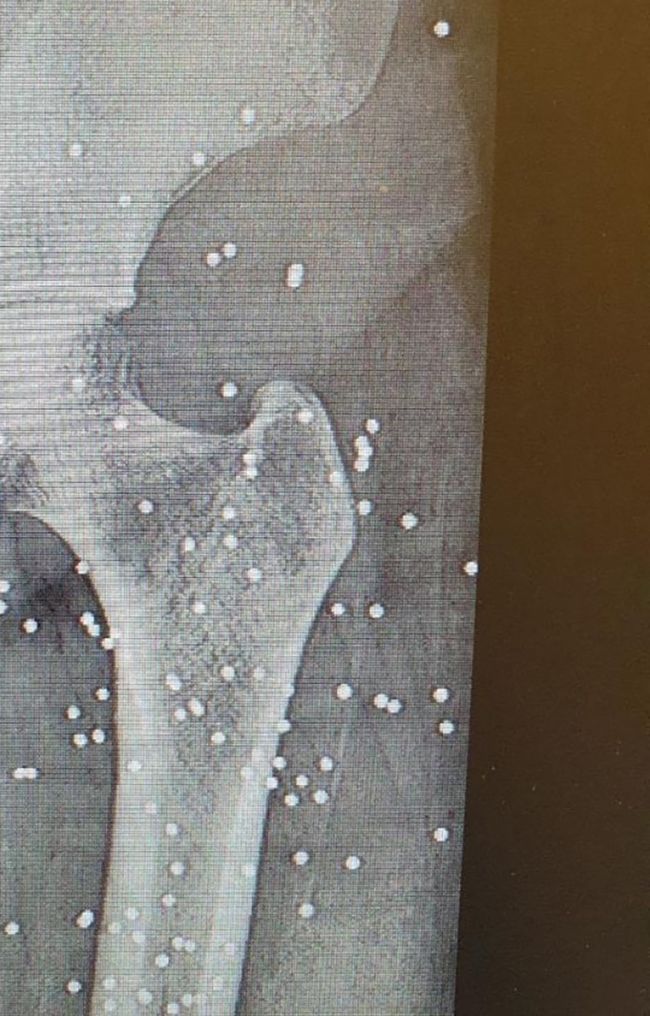

«مدرک جرم»؛ گلوله جنگی و ساچمه در بدن مردم به روایت عکسهای رادیولوژی بیمارستانهای مشهدشهرام سدیدی، شاعر و زندانی سیاسی سابق ساکن لندن، تصاویری از عکسهای رادیولوژی بیمارستان «امام رضا» مشهد را منتشر کرده است که در آنها، آثار گلولههای جنگی و ساچمه در بدن مجروحان انقلاب ملی دیده میشود.

سدیدی با انتشار این تصاویر در اینستاگرام، آنها را «سند کوچکی از جنایات» جمهوری اسلامی «با مردم شریف ایران» توصیف کرد.

شهرام سدیدی، شاعر و زندانی سیاسی سابق ساکن لندن، تصاویری از عکسهای رادیولوژی بیمارستان «امام رضا» مشهد را منتشر کرده است که در آنها، آثار گلولههای جنگی و ساچمه در بدن مجروحان انقلاب ملی دیده میشود.

سدیدی با انتشار این تصاویر در اینستاگرام، آنها را «سند کوچکی از جنایات»… pic.twitter.com/S89ELP93af